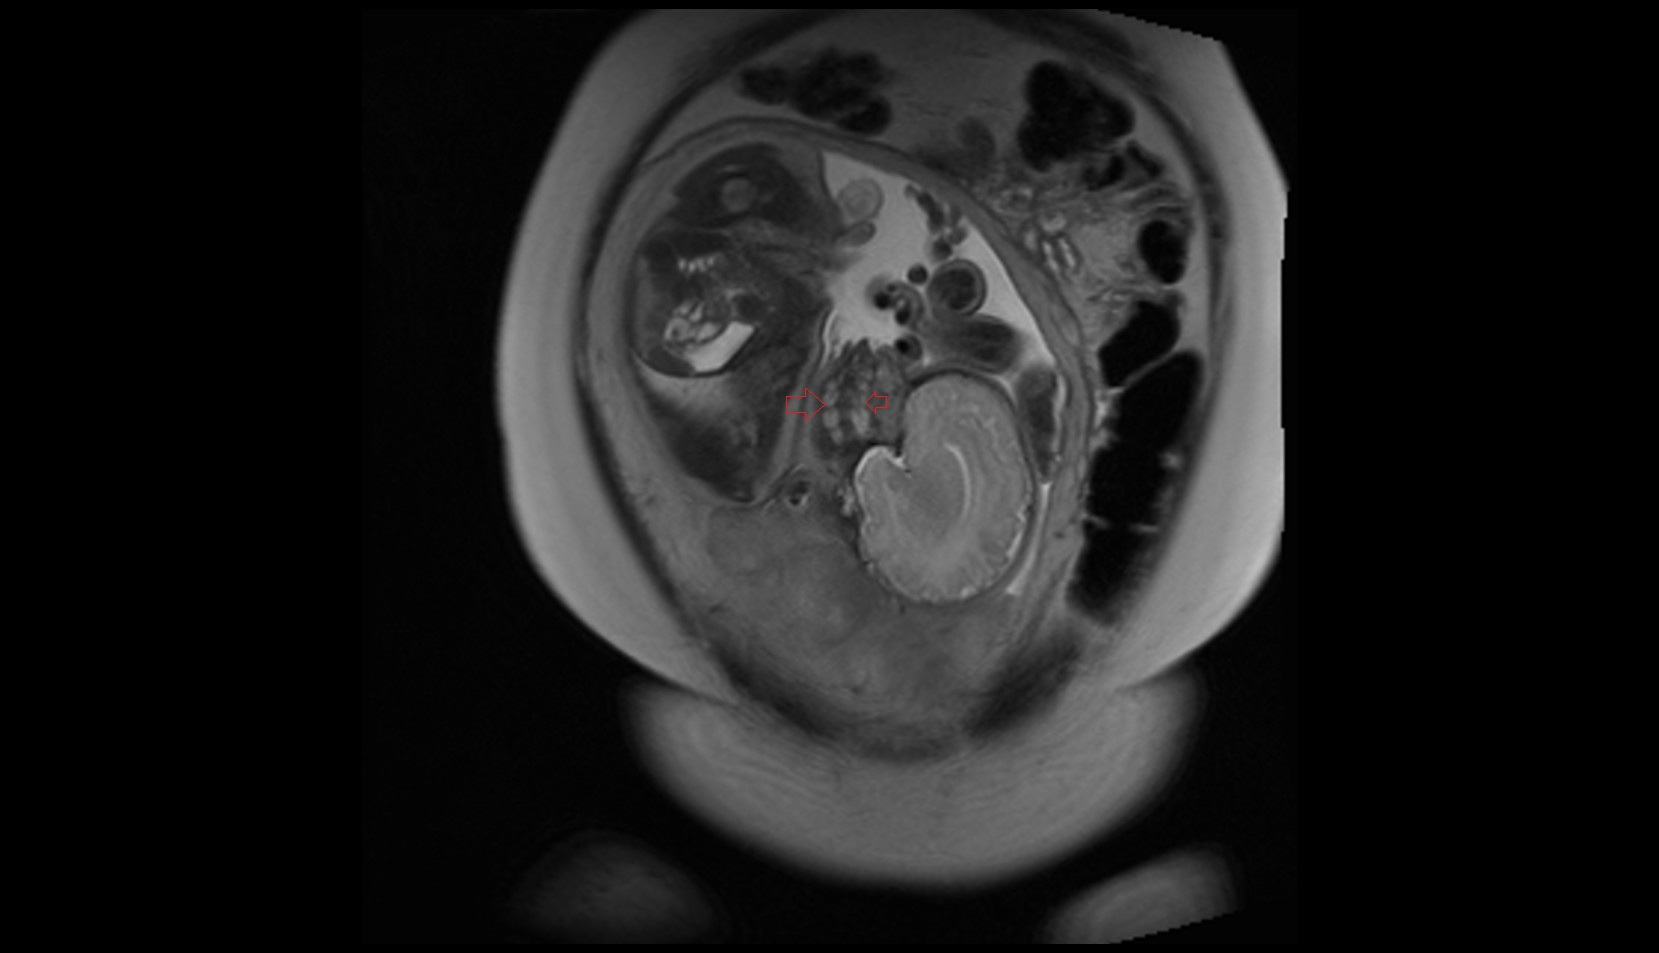

- Placenta

- Uterus (pregnancy)

- Amniotic fluid

- Umbilical cord

- Urinary Bladder in Pregnancy

- Cervix in Pregnancy

- Vagina in Pregnancy

- Fundus of uterus in pregnancy

- Fetal brain

- Maternal ovaries